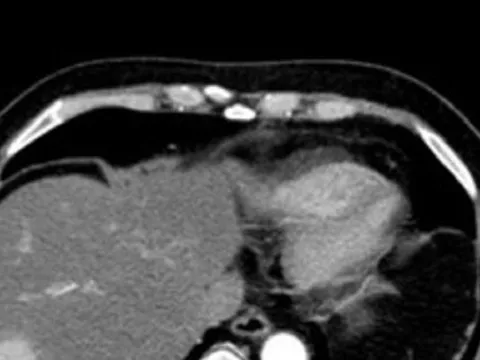

Phát hiện 'sát thủ' ung thư gan khi đi khám tim mạch

Đến bệnh viện khám tim mạch, nam bệnh nhân được bác sĩ thực hiện các xét nghiệm, kiểm tra hình ảnh thì phát hiện dấu hiệu bất thường ở gan. Kết quả chẩn đoán chuyên sâu cho thấy người bệnh bị ung thư gan. Bệnh nhân đã may mắn phát hiện ở giai đoạn sớm nên thoát “án tử”.

Phát hiện ung thư gan nhờ khám sức khỏe

Ngày 8/3, bệnh viện Hoàn Mỹ Sài Gòn tiếp nhận chẩn đoán và phẫu thuật thành công cho bệnh nhân tình cờ phát hiện ung thư gan.